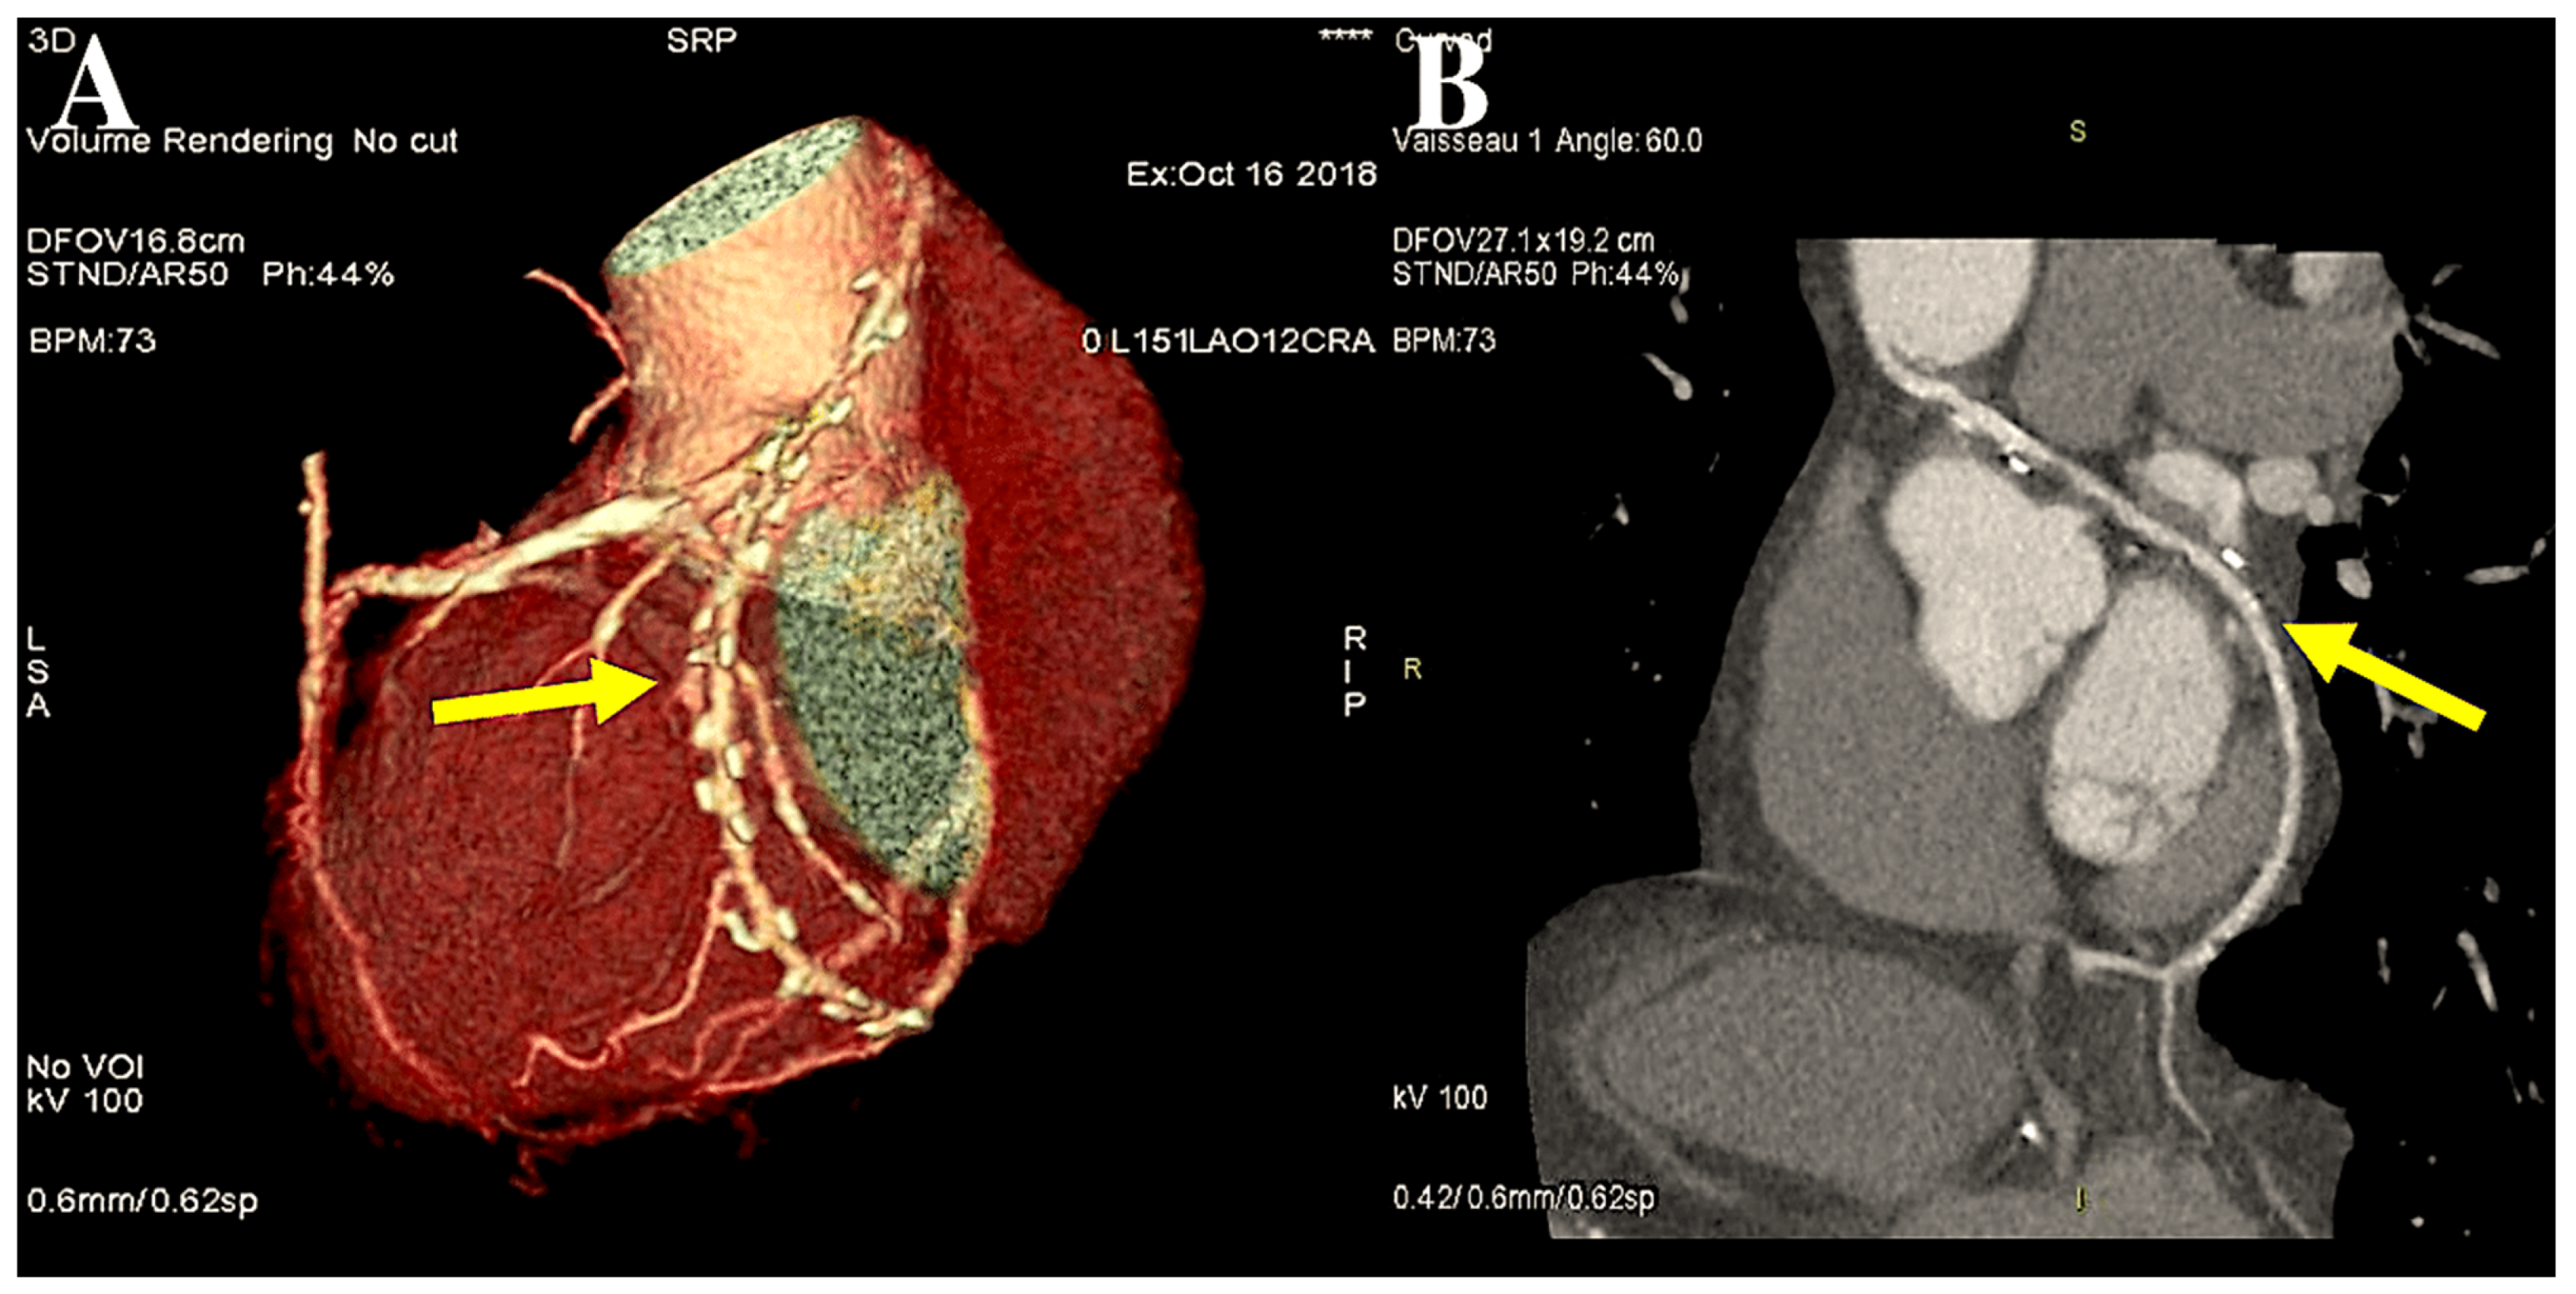

However, in cases of target vessels situated in the proximal obtuse marginal position, the graft utilised for CABG is anastomosed anteriorly or alternatively on the opposite side of the aorta through the transverse sinus (Figure 2A,B).

Figure 2.

The figure illustrates the post-processing of CT angiography of CABG using volume rendering (A) and two-dimensional curved imaging with automatic tracking. (B): CT angiographic control of the radial artery at 27 years. The radial artery (yellow arrow) was utilised as the second target conduit on the second obtuse branch of the left coronary circumflex artery and the posterior descending artery. Abbreviations: CABG, coronary artery bypass grafting; CT, computed tomography.